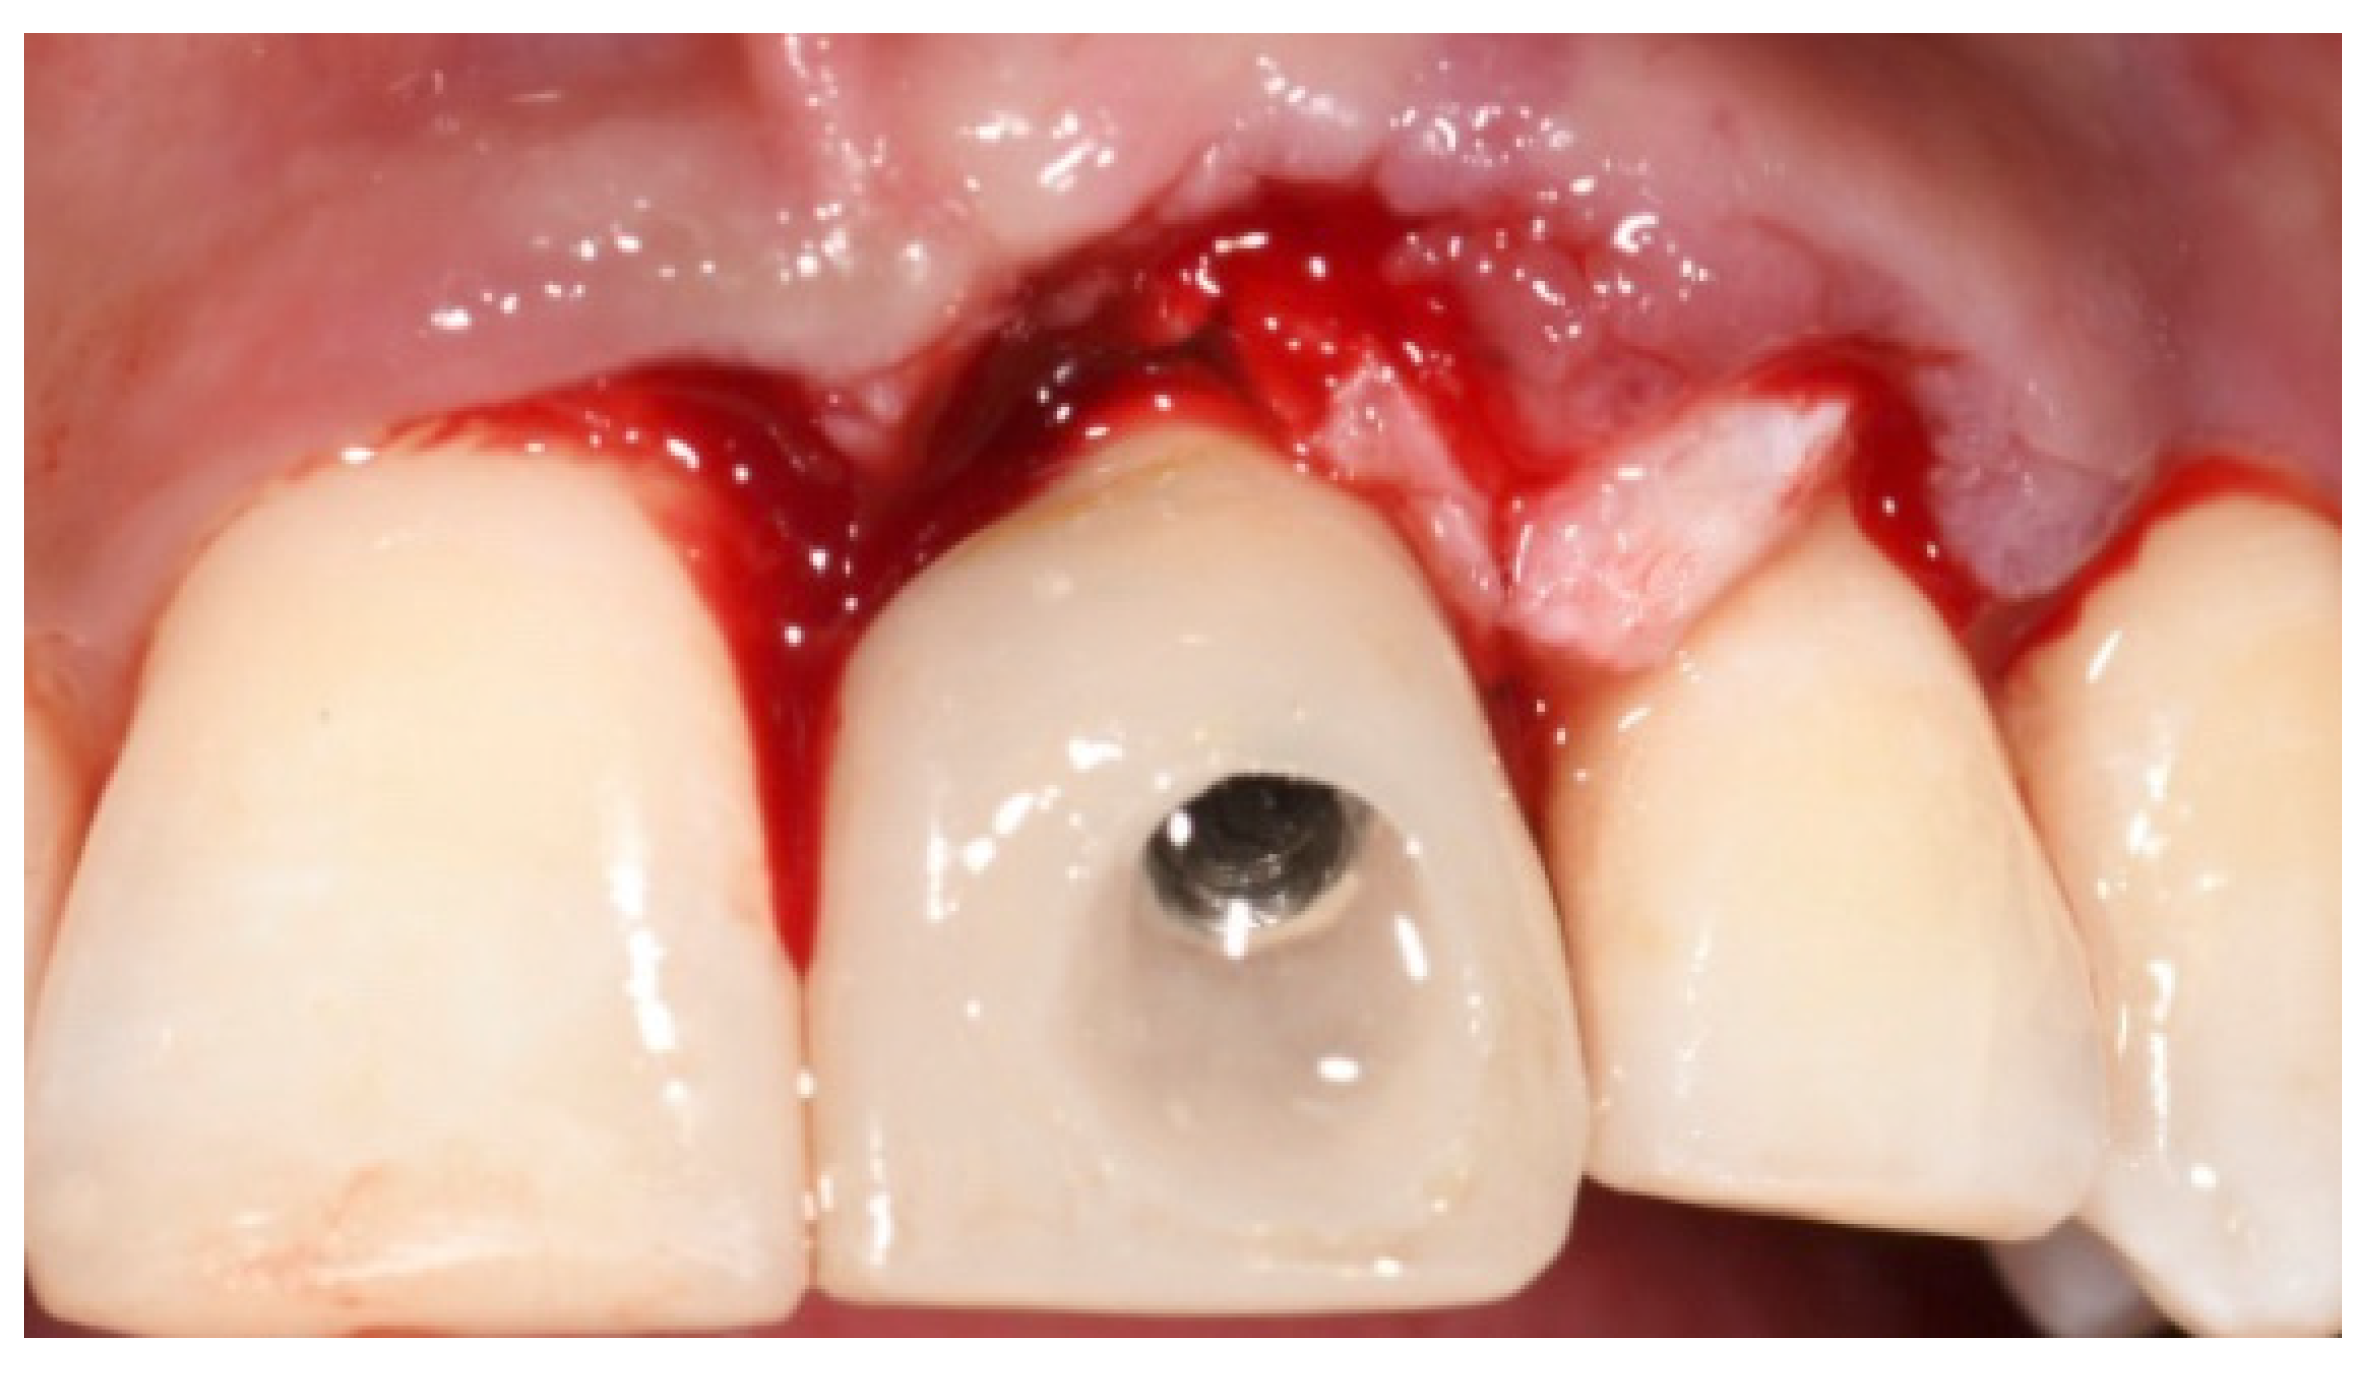

2. Case Presentation